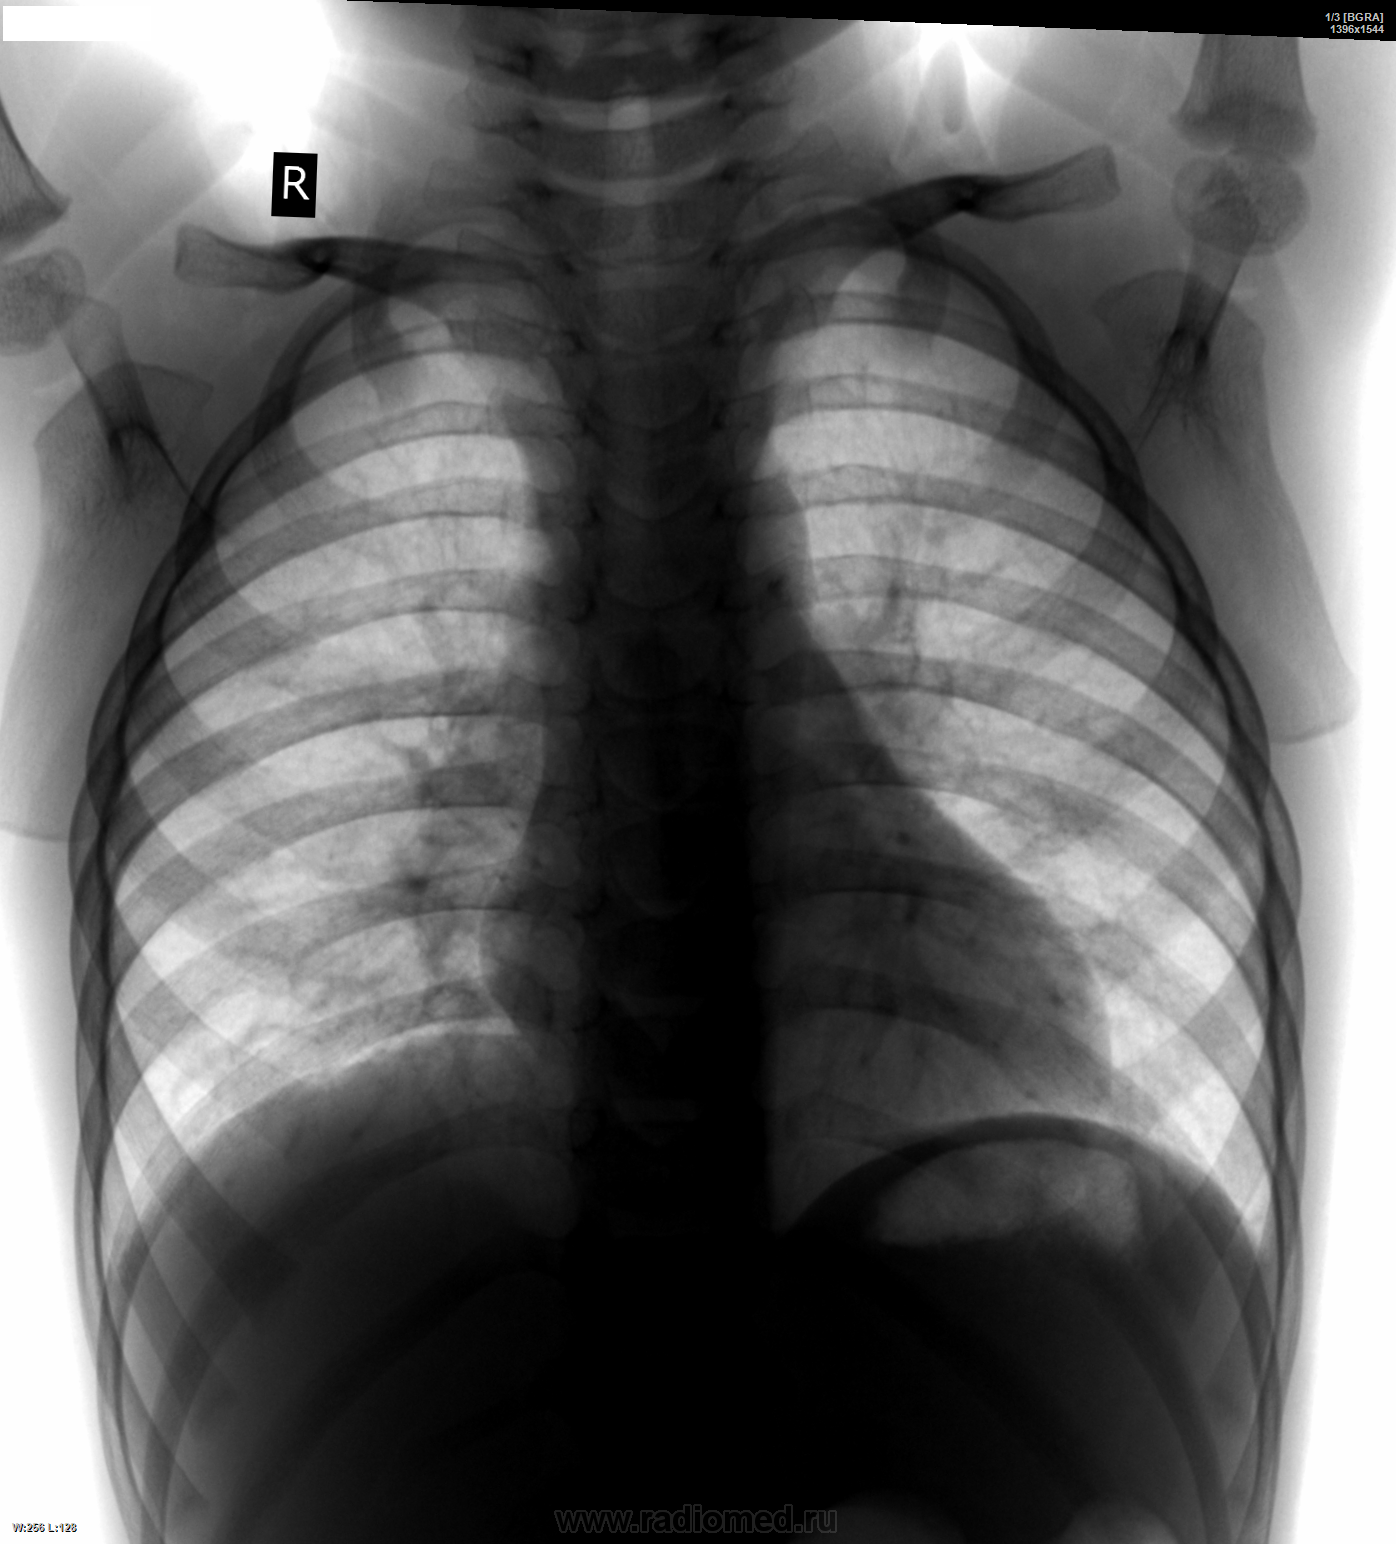

Девочка 1г7м. Кашляет со слов родителей ровно месяц. Выслушаю версии коллег - что это бронхит, ОРВИ, лимфоаденопатия или нормально почти...

Томографировать пока что нет возможности. Но тоже придрался - в правом корне что-то слегка выбухает слабой интенсивности над восходящей аортой. Пока написал ОРВИ, назначил по выздоровлении с архивом контроль...

Ребенка надо обследовать на тбс. Это не так уж сложно, но исключить надо.

Если нет возможности выполнить тмг сейчас ,то можно же направить ребенка в туб диспансер,где выполнят все необходимое.Спокойно можно заподозрить увеличение трахео-бронхиальных л/у справа +кашель в теч.1месяца,возможно,и с-мы интоксикации есть.Напрявляйте.Чего ждать?